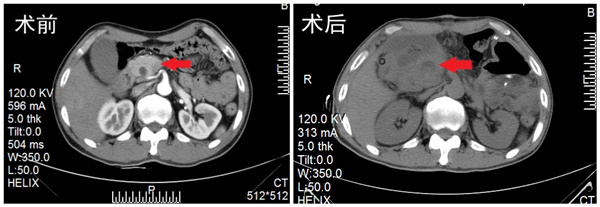

截止当天下午17时,共实施了2例胰腺癌患者纳米刀治疗。患者陈某,男,57岁,以“皮肤、巩膜黄染10天”入院,彩超提示胰腺头部实行占位,下腔静脉及肠系膜上静脉包绕。CT提示胰头癌可能,肝内外胆管扩张。血清肿瘤标记物CA19-9、CA125升高。

在进行术前对两名患者做CT引导下经皮肝穿刺胆汁外引流手术(PTCD),在肝功能得到改善后,进行开腹纳米刀消融手术。首先麻醉成功后,手术开始进行,术中超声精准测量肿瘤大小及形状,将数据输入纳米刀治疗系统,进行布针设计并优化后,在术中超声引导下将纳米刀治疗电极按预定的设计方案穿刺入肿瘤进行消融治疗。消融后,实施胆管空肠吻合解除胆道梗阻,胃空肠吻合预防消化道梗阻。手术非常成功,截止目前,2例患者均恢复顺利,未出现手术期并发症。